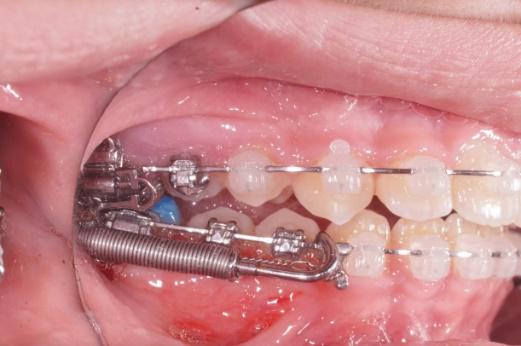

Les propulseurs permettent de corriger les déformations sévères avec un maximum d’efficacité ce sont des accélérateurs de croissance , ils sont fixes sur les bagues pendant 3 mois puis sont enlevés pour être remplacés par des élastiques.